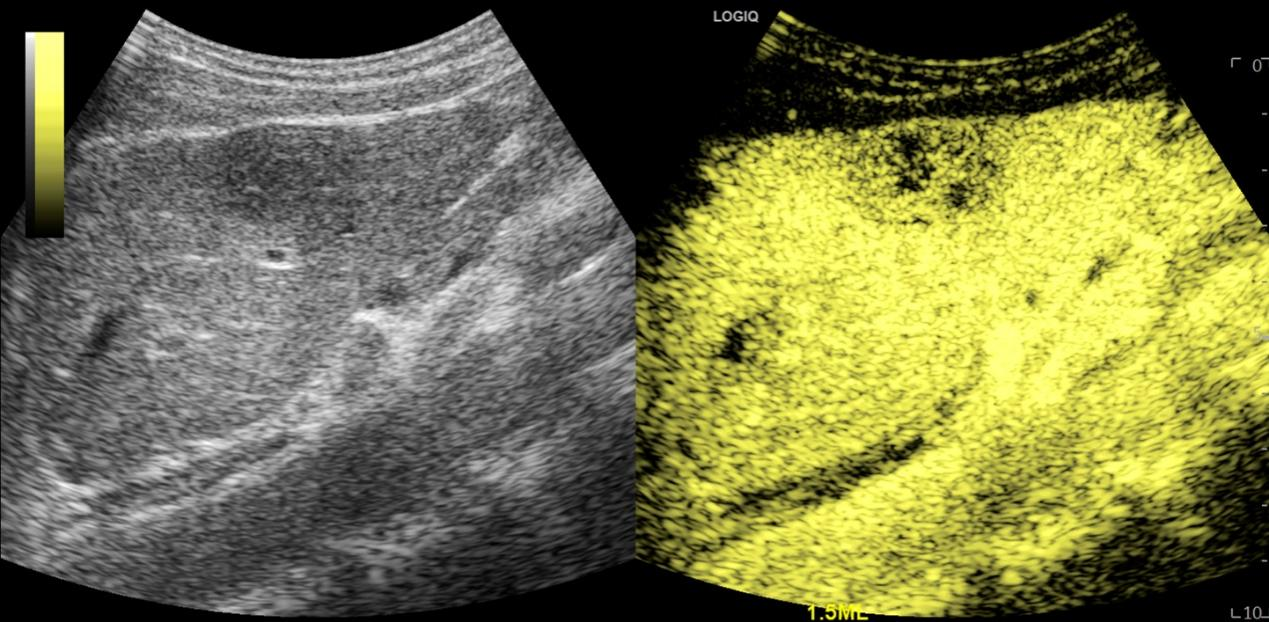

图3 肝脏肿瘤超声造影图像

超声造影是近几年来超声领域蓬勃发展的诊断新技术之一,在欧洲、美国和日本,对其临床应用价值做了大量的研究,证实超声造影的诊断能力不逊于CT和MRI,并为其规范使用制定了应用指南。

我院本部(复旦中山医院超声科)是国内最早开展肝脏疾病超声造影研究和应用的部门之一,近十年来做了大量的肝脏超声造影的临床研究,同时在胆胰肾、甲状腺和乳腺等方面也做了一定的研究,积累了丰富的临床经验,在国内外的学术期刊上发表近百篇相关论文,申请获得数十个国家级及上海市科研基金项目,成果获得国家级、上海市等多项科技奖。超声造影诊断肝脏局灶性病变准确性高,其应用价值被临床医生肯定,已常规应用于临床以明确病情。